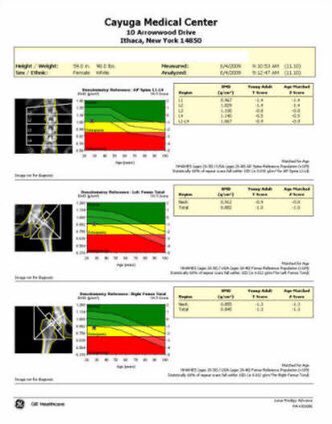

✅التشخيص المبكر مهم جداً لتفادي الكسور من خلال عمل اشعة تسمى"ديكسا"

🔻جميع النساء فوق عمر ٦٥ سنة

🔻جميع الرجال فوق عمر ٧٠ سنة

🔻وفي حال وجود عوامل خطورة مثل استخدام مركبات الكورتيزول او التهاب الروماتويد يتم عملها قبل هذه الأعمار